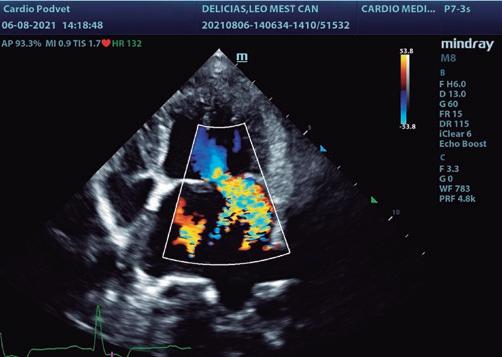

Figura 3. Corte apical 4 cámaras paraesternal izquierdo. Doppler continuo, medición de la insuficiencia mitral. Figura 2. Corte apical 4 cámaras paraesternal izquierdo. Doppler color de la insuficiencia mitral.

Se realiza una ecocardiografía donde se evidencia engrosamiento, fallo de coaptación y prolapso de las valvas de la válvula mitral (figura 1). Se determina una regurgitación mitrálica posterior grave que ocupa más del 25 % del atrio izquierdo (figura 2), con un jet excéntrico con una velocidad de 5,66 m/s (figura 3).

Existe un aumento de las dimensiones del atrio izquierdo de forma grave con un ratio LA/Ao de 2,65 y sobrecarga volumétrica. El ventrículo izquierdo está aumentado, con un LVIDd normalizado (Cornell) de 2,6 (figura 4). La función sistólica está mantenida, con una FA VI del 54 %. La función diastólica está alterada, con un patrón transmitral restrictivo con velocidad máxima del punto E mitral de 1,64 m/s.